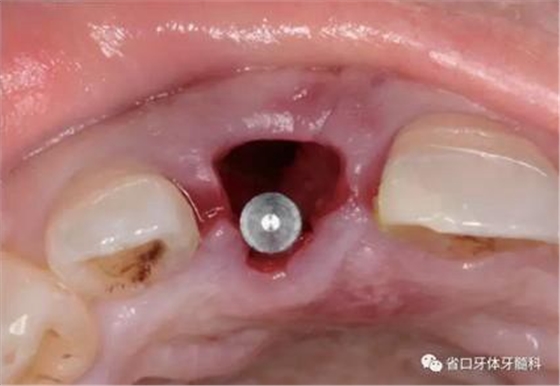

(1)微創(chuàng)拔牙及即刻種植:術(shù)前拍攝口內(nèi)照及實(shí)施牙周基礎(chǔ)治療。常 規(guī)消毒鋪巾阿替卡因局麻下微創(chuàng)拔除上頜右側(cè)中切牙,搔刮拔牙窩及根尖肉 芽組織。探測牙槽骨唇側(cè)骨壁及鄰面牙槽嵴完整,牙齦無撕裂。不翻瓣下于上頜右側(cè)中切牙缺隙近遠(yuǎn)中中點(diǎn)的腭側(cè)牙槽骨及根方定位,按照逐級預(yù)備的原則,緊貼牙槽窩腭側(cè)骨壁制備種植窩洞,植入Zimer®3.7mm×13mm TSV種植體1顆,植入扭矩>35N·cm,以O(shè)sstell測量種植體的ISQ值為68。 種植體平臺位于唇側(cè)齦緣中點(diǎn)下3mm,與唇側(cè)骨壁內(nèi)側(cè)面形成的跳躍間 隙約2mm,置入Bio-Oss®細(xì)顆粒骨粉0.25g,上愈合基臺關(guān)閉創(chuàng)口。術(shù)后 CBCT檢查顯示:種植體利用牙槽窩根方骨質(zhì)固位,緊貼牙槽窩腭側(cè)骨壁, 其唇側(cè)面與牙槽窩唇側(cè)骨壁的內(nèi)側(cè)面所形成的跳躍間隙(約2mm)可見顆 粒狀顯影物充填。牙槽窩的唇側(cè)骨壁及唇側(cè)倒凹無缺損穿孔。

圖15 植入種植體并置入覆蓋螺絲

圖16 跳躍間隙植骨

圖17 跳躍間隙植骨

圖18 測量ISQ值

圖19 術(shù)后MCT

圖20 術(shù)后開窗式取模轉(zhuǎn)移